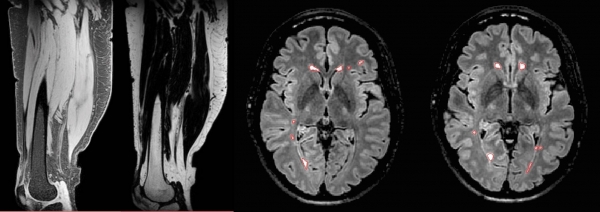

Lesion delineation and assessment is one of the focus areas of the centre. In addition to years of experience with analysis of lesions related to multiple sclerosis, the centre benefits from expertise with determining pathophysiological changes in the brain associated with small vessel disease such as white Matter Hyperintensities (WMH). Drawing on the combined skills of the group and researchers at DRCMR, the Reader Centre has further refined its sensitive and reproducible algorithms to render the evaluation of lesions and lesion size more automatic and less dependent upon subjective assessment. The image analysis technology developed by the DRCMR research groups is continuously integrated into a workflow system for rapid configuration to accommodate specific requirements. Thus, the Reader Centre offers analysis of advanced MR measures such as diffusion tensor imaging, magnetization transfer imaging (MTR), iron deposition quantification, resting-state fMRI as well as structural MRI measures, such as brain segmentation, atrophy, lesion quantification and cortical thickness. Although most studies in the Reader Centre focus on the brain, MR images of other organs are also analysed in some studies, e.g. the spinal cord and leg muscles.